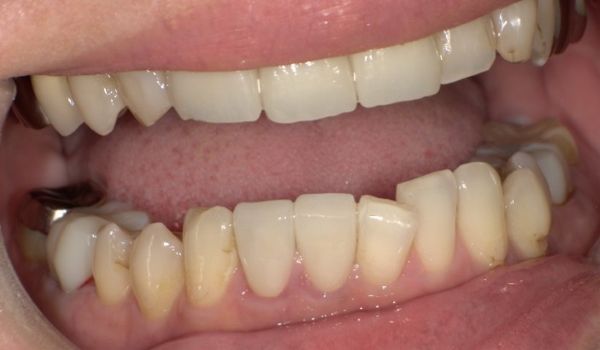

人間の歯の形態、位置、並び方などは一人として同じものはありませんし、正解もありません。今回の症例でも癒合はしていましたが、患者さんへの不都合は特になく、何度か樹脂で治療を行っていました。しかし、先頭の2本の歯をかぶせるタイミングで一緒にきれいにセラミックで治したいとのご希望でした。樹脂の詰め物は手軽に治療できる反面、経年的な色の変化や材料の劣化などが起きやすく、長期間使うことは難しい場合もあります。

当院では、仮の歯に置き換え、なるべくご希望の形態、色調に沿うようにし、被せ物を入れる方法を選択しております。仮歯に置き換えを行った後には何度か形態のすり合わせをしていき、ご希望に近い状態をめざしています。治療を行う際には歯科医師とよくご相談の上、治療を行っていただければと思います。

今回の被せ物に関しては、セラミックでの治療なので、金属を使用していないため、歯と歯茎の境目に金属色が見えてくるなどのリスクもありません。セラミックの中でも、ジルコニアセラミックを使用することで色調だけでなく、汚れがつきにくく、強度もあり、長期的に使用可能な被せ物を装着することができます。また、ご自身の歯との色の違いを最小限にするように心がけました。